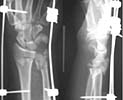

Subject: Comminuted fracture distal end forearm

40 year old bank clerk fell down from a height and suffered this closed injury to the dominant upper limb. On presentation he had numbness in the fingers pertaining to the median nerve area. Since there was a suggestion of nerve compression I have initiated the initial treatment. Would like to get your views on management. I will present what I have done after the discussion.

Attaching the initial X-ray.